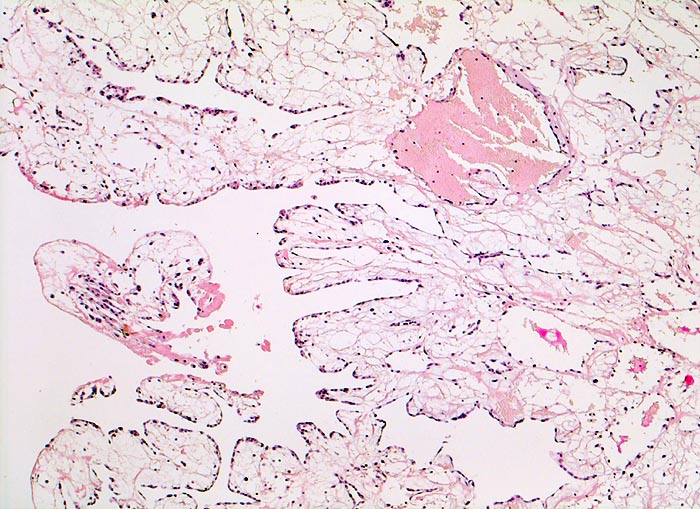

AP/ Vorhofmyxom

Vorhofmyxom